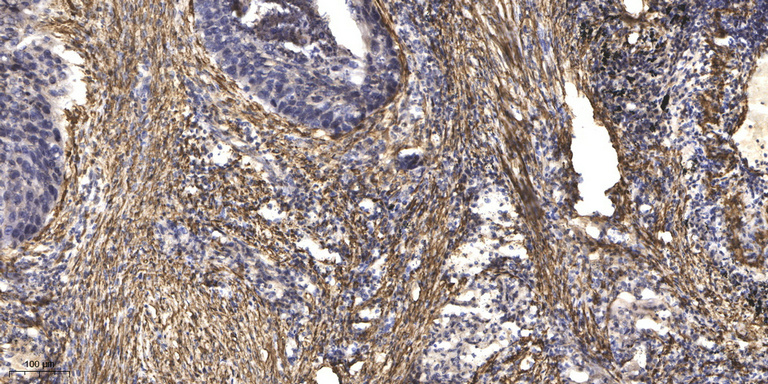

WB, IHC, IF, IP

Optimal working dilutions should be determined experimentally by the investigator; Suggested starting dilutions are as follows:IHC 1:50-300; IF 1:200.